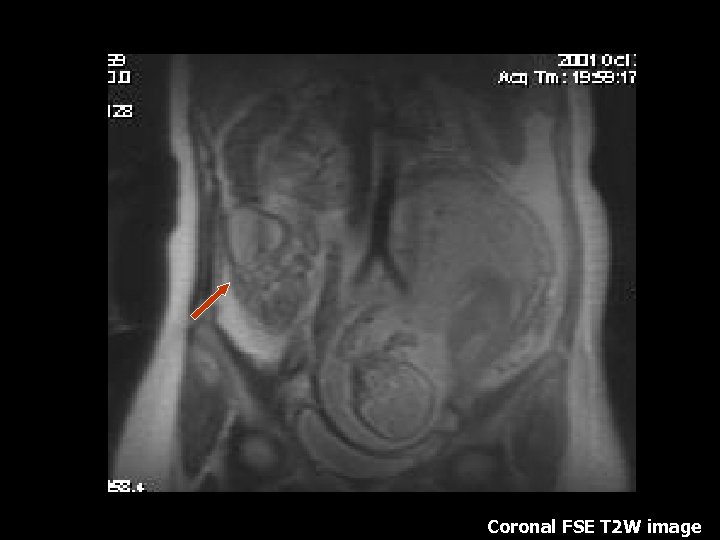

Coronal FSE T 2 W image

Colitis – Ulcerative colitis • Autoimmune disease with genetic predisposition. • Mainly affects the rectum and spreads retrograde continuously without skip lesions. • Symptoms: Intermittent diarrhea and rectal bleeding. • Complications: Toxic Megacolon and Colon Cancer • Treatment: Total Colectomy

Colitis – Ulcerative colitis • T 1 with gadolinium shows marked mucosal enhancement with sparing of the submucosa. (6). • Inflammatory tissue stranding surrounds the colon (6). • Long standing disease shows low signal intensity from submucosal edema and lymphangiectasia (6). • 30% of patients also demonstrate backwash ileitis (6).